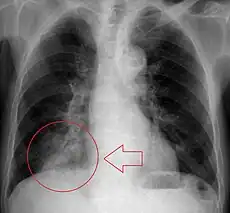

-

Obstructive pneumonia in the right lung (left side of the image) from a blockage in the respiratory tract. -

X-ray of pneumonia in lower right lung (bottom left of image) due to aspiration and airway obstruction.